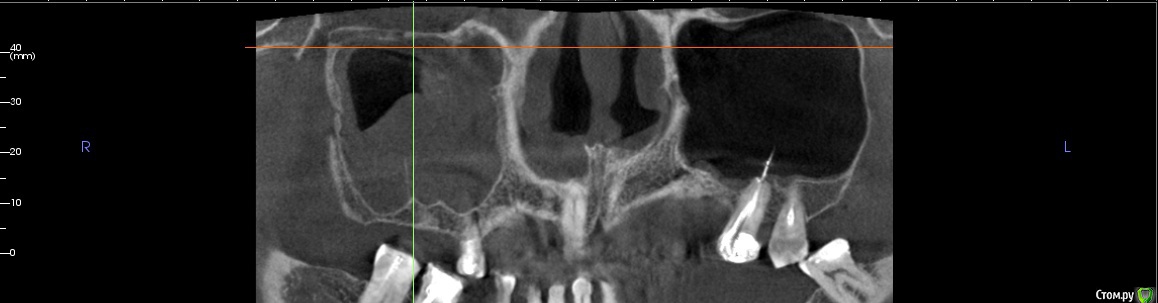

Irouil Опубликовано 16 апреля, 2018 Поделиться Опубликовано 16 апреля, 2018 Имхо - нет. ЛОР КТ смотрел вообще? Тут может быть что угодно, от уровня жидкости до инвертированной папиломы. Ссылка на комментарий

kamranchick Опубликовано 16 апреля, 2018 Автор Поделиться Опубликовано 16 апреля, 2018 Смотрел, и такое заключение дал. вот меня и смутило, в верхней трети около соустя вообще вкрапления какие то есть )) Ссылка на комментарий

Irouil Опубликовано 16 апреля, 2018 Поделиться Опубликовано 16 апреля, 2018 Смотрел, и такое заключение дал. вот меня и смутило, в верхней трети около соустя вообще вкрапления какие то есть ))Больше всего похоже на грибковое тело, и вкрапления эти намекают, и контуры затенения. Пунктировать не стал ЛОР это? 1 Ссылка на комментарий

kamranchick Опубликовано 16 апреля, 2018 Автор Поделиться Опубликовано 16 апреля, 2018 Больше всего похоже на грибковое тело, и вкрапления эти намекают, и контуры затенения. Пунктировать не стал ЛОР этоОтправил для санации, он написал вот это только( что ретенционная, но потом я внимательно начал крутить туда сюда и вот засомневался Ссылка на комментарий

Irouil Опубликовано 16 апреля, 2018 Поделиться Опубликовано 16 апреля, 2018 По большому счету; какая разница то? Вы же пациентку ради синус лифта (насколько я понимаю) отправляли, в таких условиях его не сделать. Там даже если соустье толщиною с пенис Трампа будет, все равно его ткани+отек перекроют после синуса. Так или иначе пазуху надо оперировать, только если ЛОР не считает что ретенционная киста - одонтогенная и пройдет при санации первичного очага) Ссылка на комментарий